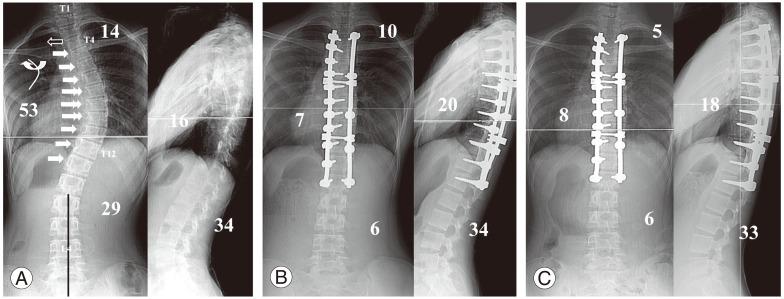

We retrospectively analyzed 160 patients with thoracic adolescent idiopathic scoliosis treated by pedicle screw instrumentation and rod derotation. Patients who had a distal fusion level between T11 and L1 were divided into two groups: the DVR group versus the No-DVR group. Each group was divided into subgroups depending on the lumbar modifier used: the DVR-A, B, and C groups versus the No-DVR-A, B, and C groups. The DVR-A group was subdivided into two subgroups depending on the direction of screw rotation in the LIV: the DVR-A-O group (opposite direction) and the DVR-A-S group (same direction).

There were no significant differences in the preoperative curve characteristics between the two groups. The preoperative lumbar curve was corrected in 70% of the patients in the DVR group and in 56% in the No-DVR group. Spontaneous coronal correction of the lumbar curve was better in the DVR-A-S group than that in the No-DVR-A group. However, the DVR-A-O group had the higher incidence of adding-on deformity. The DVR-B and C groups showed better spontaneous correction of lumbar coronal magnitude, apical vertebral translation, and rotation and the LIV tilting.

In lumbar modifiers B and C, screws in the LIV have to be rotated opposite to the direction of the screw rotation of the main thoracic curve; however, in modifier A, the screws have to be rotated in the same direction.

我们回顾性分析了160例接受椎弓根螺钉内固定和棒旋转术治疗的青少年特发性脊柱侧凸患者。远端融合水平在T11和L1之间的患者分为两组:DVR组和非DVR组。每组根据使用的腰椎修正器分为亚组:DVR - A、B和C组与非DVR - A、B和C组。DVR - A组根据LIV中螺钉旋转方向再分为两个亚组:DVR - A - O组(相反方向)和DVR - A - S组(相同方向)。

两组术前曲线特征无显著差异。DVR组70%的患者术前腰椎曲线得到矫正,非DVR组为56%。DVR - A - S组腰椎曲线的自发冠状面矫正优于非DVR - A组。然而,DVR - A - O组附加畸形的发生率更高。DVR - B组和C组在腰椎冠状面大小、顶椎平移、旋转和LIV倾斜方面显示出更好的自发矫正效果。

在腰椎修正器B和C中,LIV中的螺钉必须与主胸弯螺钉旋转方向相反;然而,在修正器A中,螺钉必须朝相同方向旋转。